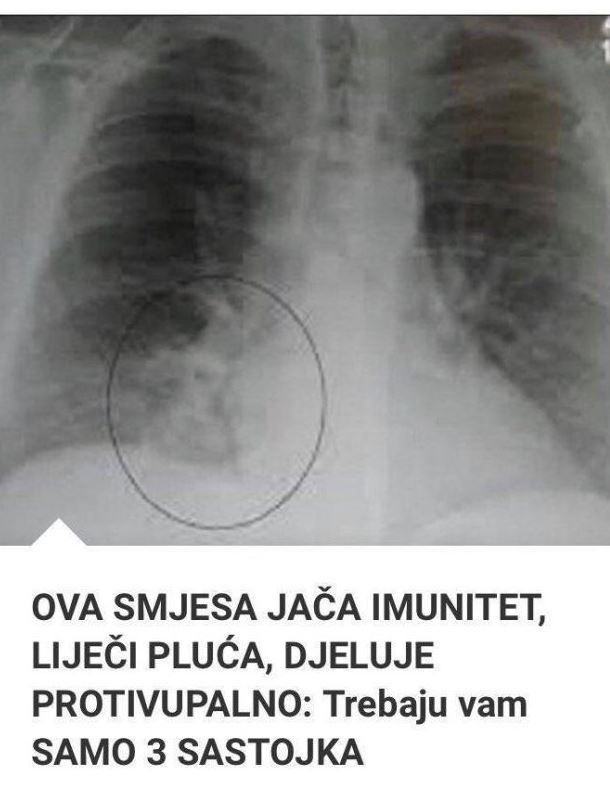

U periodima kada su prehlade i virusi česta pojava, važno je pronaći prirodne metode za očuvanje zdravlja. Jedan od najjednostavnijih i najučinkovitijih načina za to jeste konzumiranje zdravih napitaka koji jačaju organizam. Među njima se posebno ističe napitak od praziluka, koji ne samo da ima moćna protivupalna svojstva, već i doprinosi zdravlju respiratornog sistema.

Osim toga, praziluk blagotvorno utiče na pluća, probavu, jetru, bubrege i cirkulaciju, pomaže u iskašljavanju i ublažavanju simptoma astme i upale pluća. Takođe, doprinosi regulaciji holesterola i boljem radu bubrega.

Iako se praziluk može koristiti u ishrani na razne načine, najbolje koristi pruža kada se konzumira u obliku soka, u kombinaciji sa jabukama i đumbirom. Ovaj napitak ne samo da jača imunitet, već i osigurava organizmu potrebne vitamine i minerale.

Kombinacija praziluka, jabuka i đumbira pruža brojne benefite za organizam, od jačanja imuniteta do zaštite pluća i smanjenja upala. Ovaj jednostavan, ali moćan napitak, može vam pomoći da očuvate zdravlje i vitalnost. Uvrstite ga u svoju rutinu i uživajte u njegovim blagodatima!